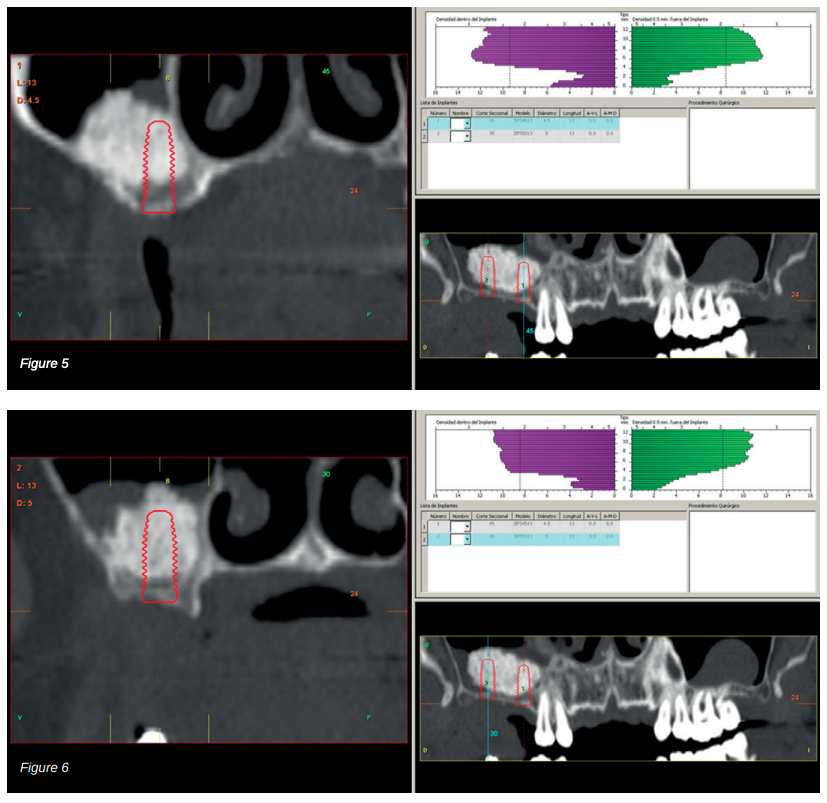

Therefore, it was decided to carry out a sinus lift using biomaterial (bovine hydroxyapatite) bound to PRGFEndoret. The elevation was performed and after five months a new dental cone beam displayed the quantity and quality of the graft obtained for the insertion of dental implants. In the cuts corresponding to the molars of the first quadrant, we observed excellent consolidation of the graft with space to insert 13 mm implants. Today, we would not choose this implant length, since studies published by our group with short and extra-short implants support their use, in addition to showing their diameter is more important than the length to distribute the loads of an already integrated implant; where an 8.5 mm length implant would work in the same way as a 13 mm implant of the same diameter18.

Back in 2007, the therapeutic protocol for these cases was very different (Figures 5-7), with short implants without full development – and without studies demonstrating the importance of diameter over implant length – efforts were focused on the search for anchorage by implant length instead of looking for the bicortical (vestibular-lingual) stability that short and wide implants perform. During this time, the failure of molars 46 and 47 also occurred; these were also extracted and replaced with dental implants.